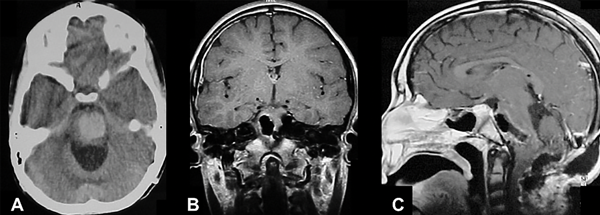

Figura 5. MC cerebral infratentorial cerebelosa. Paciente femenino de 15 años, consulta por síndrome cerebeloso. A) TC de cerebro que muestra imagen espontáneamente hiperdensa en región vermiana y pedúnculo cerebeloso medio izquierdo. B) RM secuencia T2 que muestra lesión heterogénea con edema perilesional. C) RM secuencia T1 con contraste EV en plano coronal que muestra la relación de la MC con el receso superolateral. D) RM-SWI que muestra lesión con componentes hemáticos. E-F) RM postquirúrgica cerebral, secuencia T1 con contraste EV, se muestra resección completa de la malformación cavernosa.

Figura 6. MC medular a nivel T10. Paciente masculino de 15 años que ingresa por paraplejía progresiva de varios días de evolución y compromiso de esfínteres. A) RM de columna dorsolumbar corte sagital T2-STIR que evidencia lesión heterogénea, compatible con MC. B) RM corte axial T2-STIR. C-D) RM de cerebro secuencias SWI y T2 que muestra otra lesión en hemisferio cerebeloso derecho. Por la severidad del cuadro clínico se realizó cirugía de urgencia. E-F) RM de columna dorsolumbar postquirúrgica, secuencias T1 y T2-STIR donde se observa el lecho quirúrgico libre de lesión. Se observa laminectomía del nivel T10. El paciente tuvo una recuperación parcial del foco neurológico. Actualmente en rehabilitación.

En nuestra serie presentamos un único caso de lesión espinal sintomática, con lesión intracraneal concomitante asintomática (ver Figura 6). El paciente se presentó con cuadro motor de más de 72 horas de evolución, llegando a la consulta con paraplejia, nivel sensitivo y alteraciones esfinterianas. Se instauró tratamiento de exéresis total de urgencia, en concordancia con la bibliografía. Se obtuvo una recuperación motora parcial, requiere de ayuda para las actividades de la vida cotidiana, sin recuperación de sensibilidad ni esfínteres.